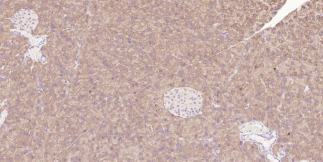

Immunohistochemical analysis of paraffin embedded rat pancreas tissue slide using IHC0329R (Rat LGR5/GPR49 Kit).